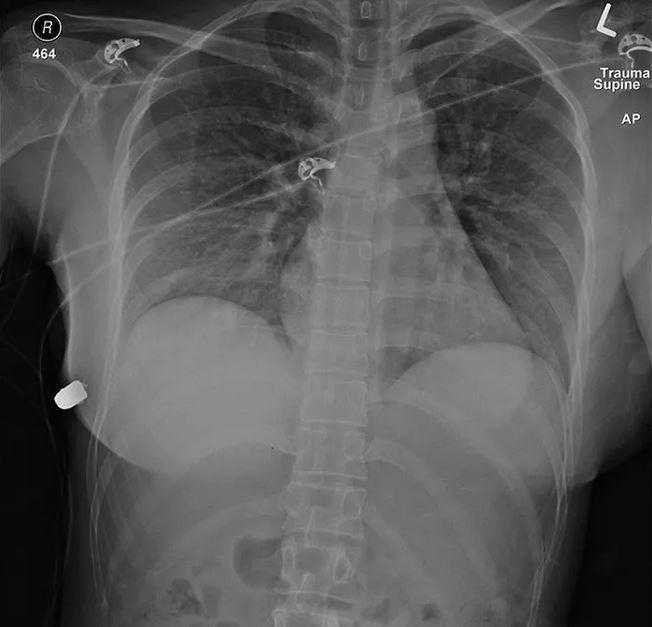

Ao se examinada, foi encontrado um ferimento de entrada no lado direito. Foi aí, então, que o inesperado aconteceu. Após passar por uma série de exames, os médicos descobriram uma bala alojada no seio esquerdo da mulher.

Mas mais do que isso: exames de imagem mostraram que a bala entrou pelo seio direito, acabou sendo desviada e desacelerada pelos implantes de silicone, e acabou se alojando no implante do lado esquerdo. O impacto foi tamanho que a prótese esquerda acabou virando pelo contrário.

“A prótese de silicone provavelmente foi responsável por desviar a trajetória da bala e salvar a vida da mulher. Com base na trajetória de entrada da bala, a única fonte de deflexão do projétil foi o implante da mama esquerda.

Esse implante cobre o coração e a cavidade intratorácica e, portanto, provavelmente salvou a vida da paciente”, escreveram os especialistas no artigo.